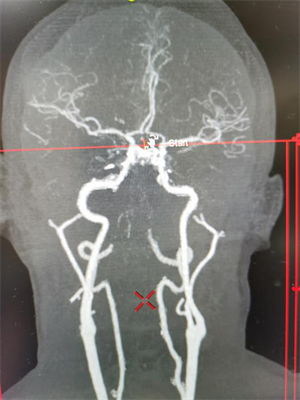

经快速沟通,家属签字同意后,静脉溶栓药物开始使用,同时病情报告给神经内科脑血管介入团队,在保持呼吸道通畅等措施下进行急诊CTA检查,在静脉溶栓药物使用结束时,患者的CTA检查结果出来,证实是急性脑梗死,基底动脉闭塞。与患者家属沟通颅内动脉取栓风险与获益,家属同意手术。

在麻醉科及脑血管介入团队的积极配合下,15:35股动脉穿刺成功,造影发现基底动脉闭塞,经导管抽吸取出血栓一枚,15:56血管再通,复查造影显示基底动脉中下段重度狭窄,后在狭窄段置入血管支架一枚。手术顺利,当晚患者神志转清醒。